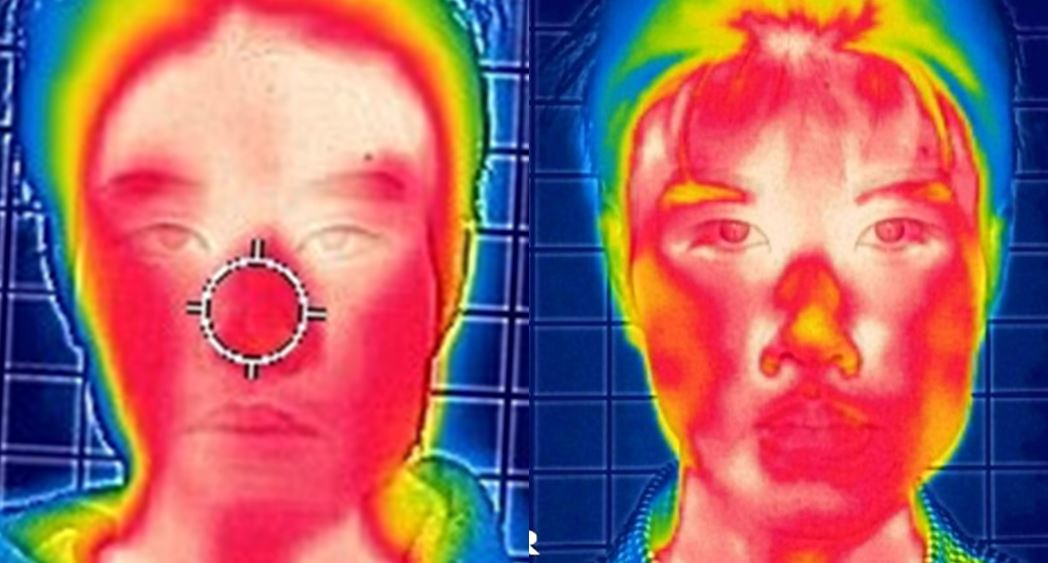

Not long ago, a practicing physician from Prague visited my clinic during orthodontic bracket treatment. She was diagnosed with facial asymmetry and body misalignment, and experienced MCB splint therapy. She was aware that bodily misalignment is related to asymmetry in the facial bones.